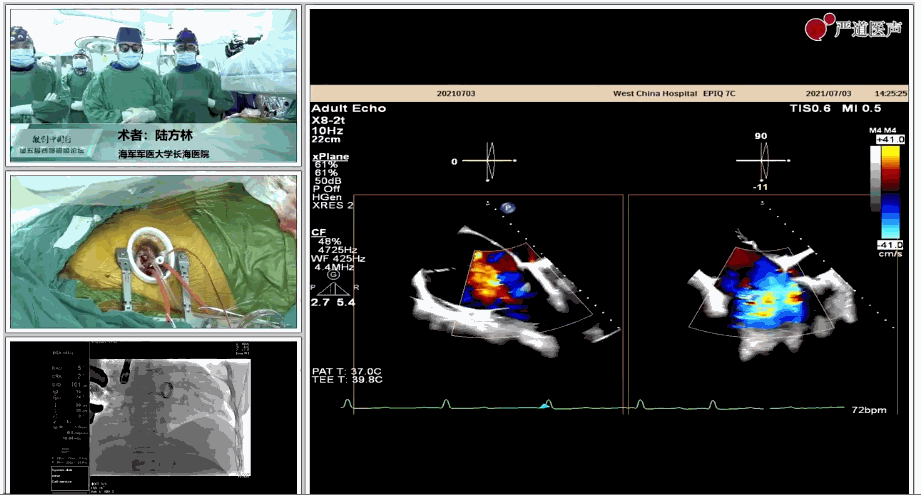

7月3日下午,海軍軍醫(yī)大學(xué)附屬上海長(zhǎng)海醫(yī)院心血管外科徐志云、陸方林團(tuán)隊(duì)在論壇中分享了經(jīng)導(dǎo)管三尖瓣置換術(shù)(LuX-Valve®)的手術(shù)直播演示。線下會(huì)議由陶涼教授、潘文志教授、喬晨暉教授共同參與討論和臨床分享。

陸方林教授分享的是一例極重度三尖瓣返流的患者采用健世科技(LuX-Valve®)經(jīng)導(dǎo)管三尖瓣置換系統(tǒng)進(jìn)行的手術(shù)直播演示。此例患者為69歲女性,入院前17年行二尖瓣機(jī)械瓣置換術(shù),術(shù)后長(zhǎng)期服用華法林抗凝,既往“2型糖尿病”病史5年,“雙下肢水腫”3年。3個(gè)月前患者出現(xiàn)腹脹、雙下肢水腫,伴活動(dòng)后暈厥,伴黃疽、皮膚濕癢、牙齦出血,癥狀持續(xù)加重,遂入院治療。入院后行心臟CT、心臟超聲檢查,提示:“三尖瓣關(guān)閉不全(極重度),二尖瓣置換術(shù)后,心功能III級(jí)”。徐志云、陸方林微創(chuàng)三尖瓣置換團(tuán)隊(duì)對(duì)該患者的病情進(jìn)行了充分的評(píng)估和討論。由于患者有開胸二尖瓣置換手術(shù)史,且病史時(shí)間長(zhǎng),同時(shí)存在相關(guān)合并癥,傳統(tǒng)外科手術(shù)風(fēng)險(xiǎn)極高(STS評(píng)分:8.315%),最終決定采用三尖瓣LuX-Valve®瓣膜系統(tǒng)對(duì)患者進(jìn)行治療。

▲術(shù)中食道超聲顯示三尖瓣極重度返流